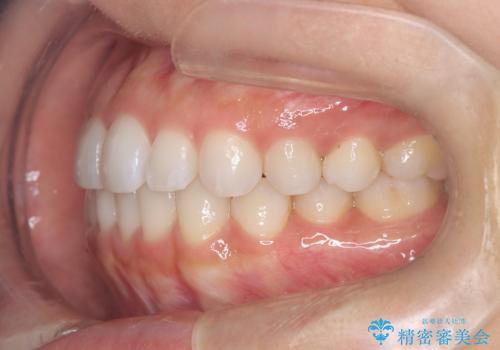

前歯の叢生を非抜歯で改善|インビザライン+IPR・遠心移動・FIX保定

- 前歯部のガタガタ(叢生)を非抜歯で改善するため、インビザラインによるマウスピース矯正を計画しました。抜歯は行わず、歯間をわずかに削るIPR(ディスキング)と奥歯を後方に移動させる遠心移動を併用して、歯を並べるスペースを確保します。歯列が整った後は、FIXリテーナー(固定式保定装置)で後戻りを防止し、安定した歯並びを維持します。

歯を抜きたくないというご希望に応え、インビザラインを用いて非抜歯で歯列を整えました。前歯に必要なスペースを確保するため、歯間をわずかに削るIPRと奥歯を後方に移動する遠心移動を組み合わせました。これにより自然で美しい歯並びを実現。治療終了後は、歯の裏側に目立たないFIXリテーナーを装着し、歯列の後戻りを効果的に防ぎました。患者様は治療中も審美的にストレスなく過ごされ、満足度の高い結果を得られました。